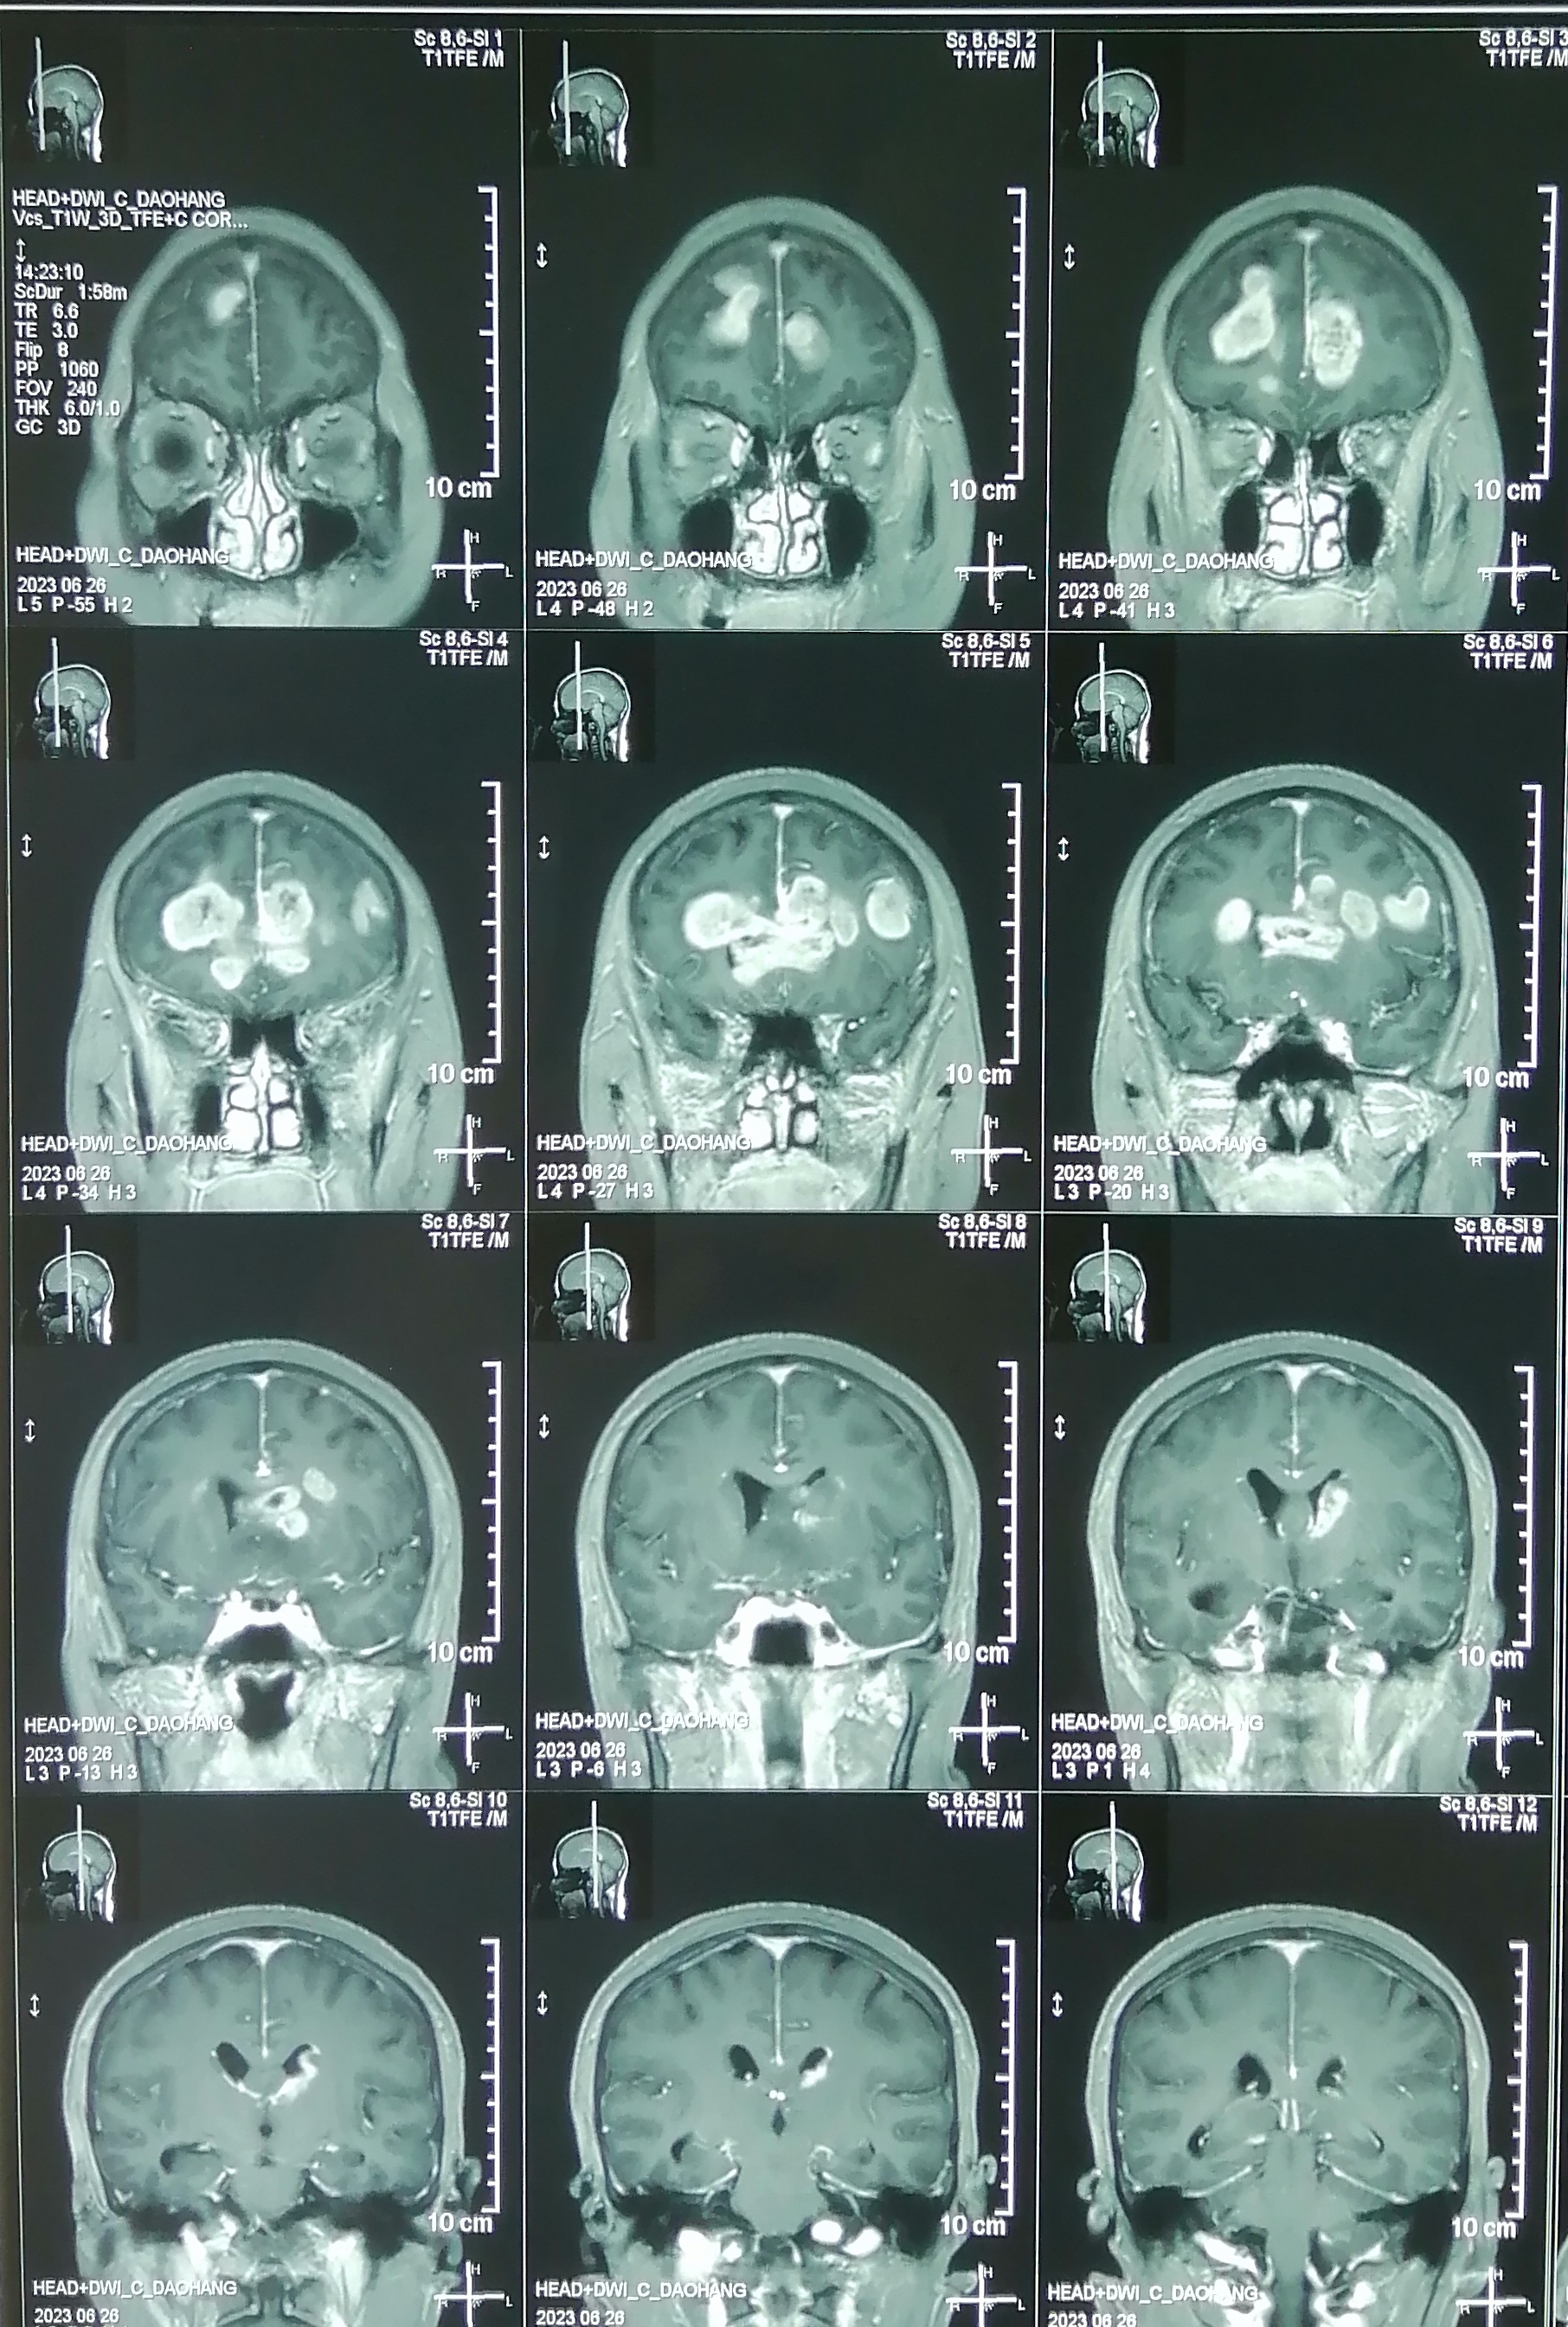

术前增强核磁:

片子可见肿瘤多中心, 累及范围广,包括胼胝体膝部,穹窿体,下丘脑,双侧额叶,左侧脑室前壁。